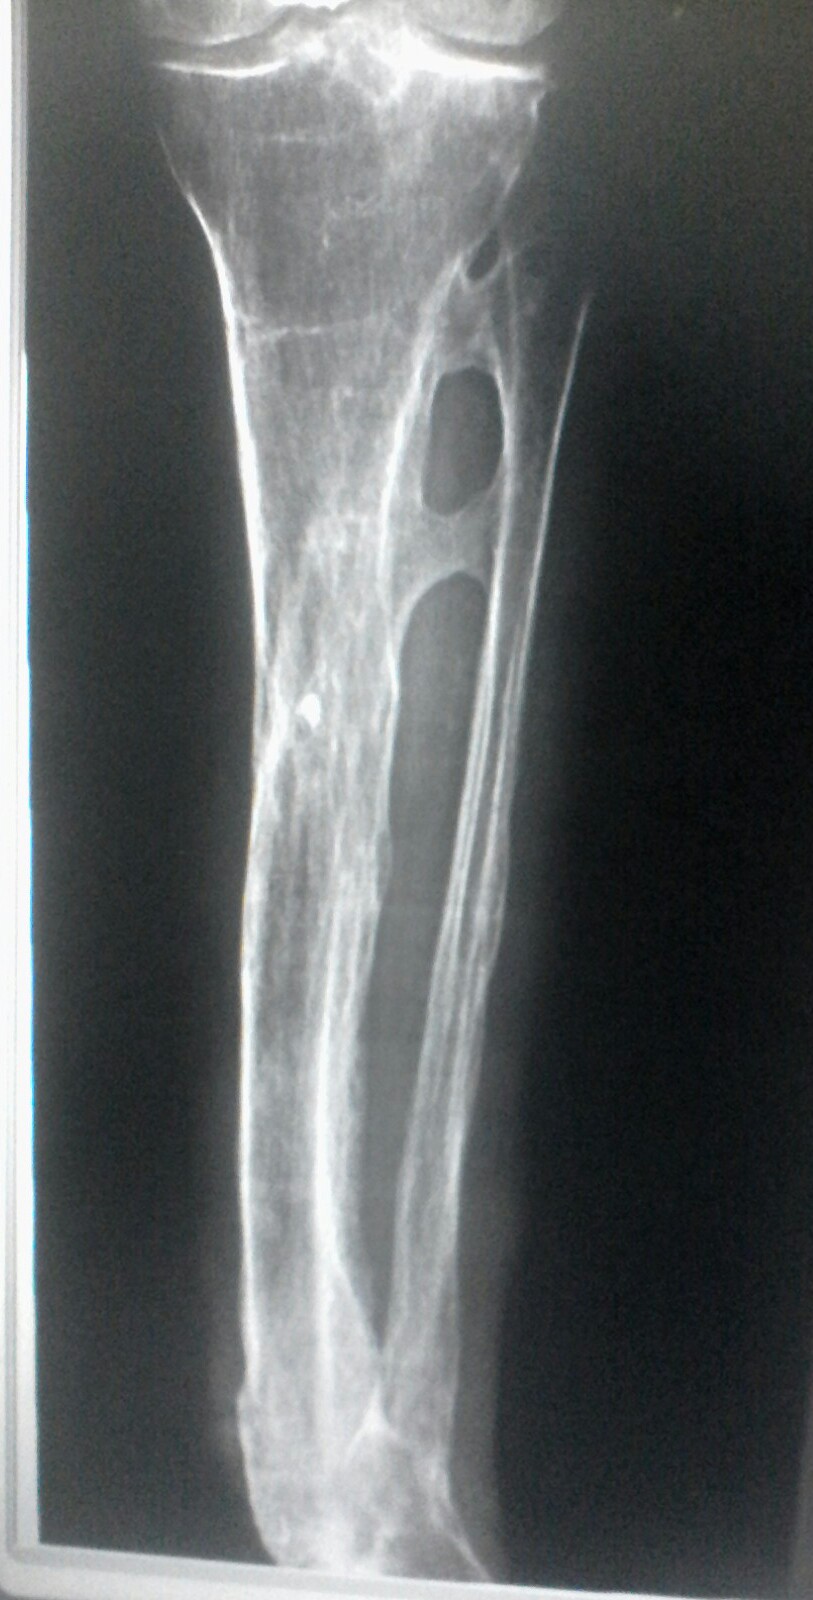

A rx study was performed on an 86-year-old female patient who suffered a rat bite and months later discovered that the infection had spread to the bones of her left leg affecting specifically the tibia and fibula and was diagnosed with osteomyelitis. The study was remitted weeks later to discover the presence of larvae that fed on the spongy tissue of the bones in order to see, after the extraction of some larvae, if there was still presence of these.